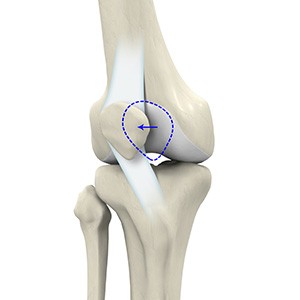

The patella is a small piece of bone in front of the knee that slides up and down the groove in the femur bone during bending and stretching movements.

Patellofemoral instability means that the patella (kneecap) moves out of its normal pattern of alignment. This malalignment can damage the underlying soft structures such as muscles and ligaments that hold the knee in place.

Lateral patellar instability is defined as a lateral shift or displacement of the patella (kneecap) as a result of disruptive changes in the medial patellofemoral ligament (MPFL) and medial patellar retinaculum.

The patella (kneecap) is a protective bone attached to the quadriceps muscles of the thigh by quadriceps tendon. It articulates with the femur bone to form the patellofemoral joint. The patella is protected by a ligament called the medial patellofemoral ligament (MPFL), which prevents the kneecap from gliding out.